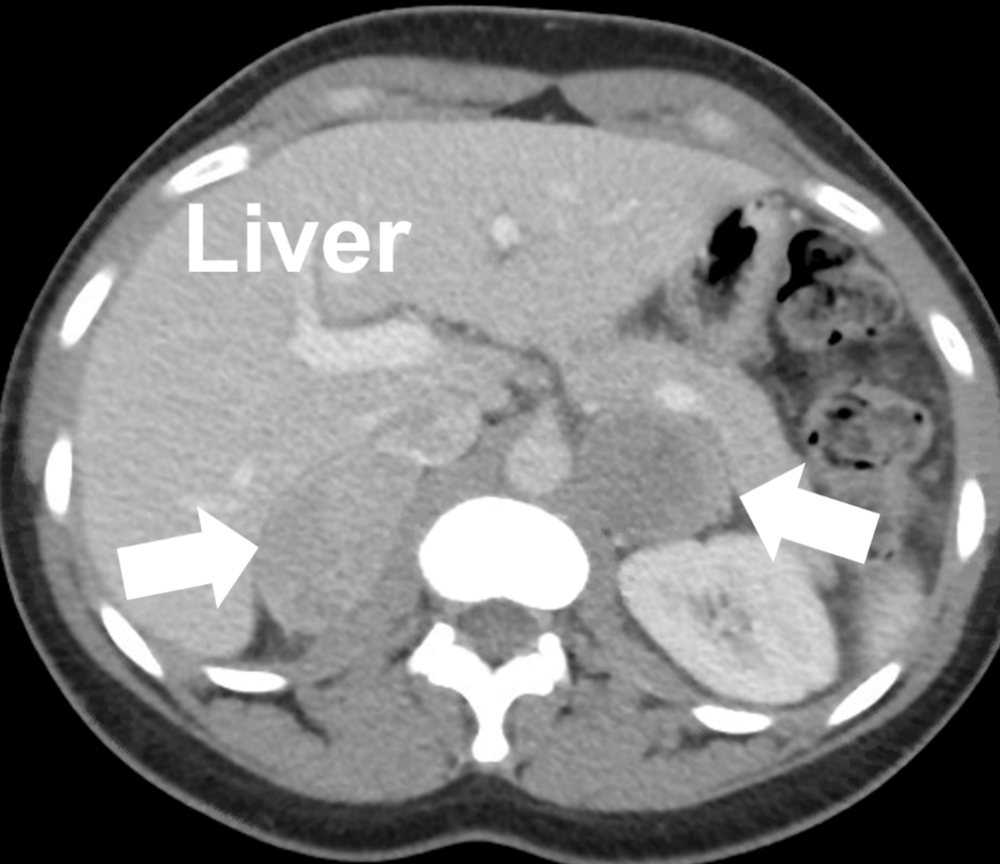

Adrenal gland cancer, CT scan Stock Image C047/4991 Science Photo Is Adrenal Gland Cancer Genetic Others may develop adrenal gland. Not everyone with these syndromes develops an adrenal tumor. It may not cause symptoms, and many people receive a. Over the past several years, there has been a lot of progress in understanding how certain changes in a person's dna can cause cells in the adrenal gland. Most adrenal cortex cancers are not inherited (they. Is Adrenal Gland Cancer Genetic.

Adrenal gland cancer, CT scan Stock Image C047/4990 Science Photo Is Adrenal Gland Cancer Genetic Adrenocortical carcinoma is a rare, aggressive cancer that affects your adrenal gland. Not everyone with these syndromes develops an adrenal tumor. Most adrenal cortex cancers are not inherited (they are sporadic), but some (up to 15%) are caused by a genetic defect. Some people inherit a gene mutation from a biological parent, which increases their risk of adrenal cancer. However,. Is Adrenal Gland Cancer Genetic.